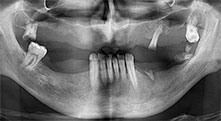

Bratu: We routinely use the instruments for harvesting bone blocks and splitting alveolar ridges. We also use the Piezomed B6/B7 for osteotomy of impacted teeth and removing failed implants. All indications that require deep, clean cuts.

Bratu: We like to use the sandwich technique for augmentation in the lateral mandible. A bone cover is prepared with the piezo saw and the crestal fragment is fixed with microscrews. We place a mixture of autologous bone and xenogenic bone replacement material in between. This works very reliably. You should always ensure sufficiently dimensioned vertical cuts when splitting the alveolar ridge in the mandible. Otherwise the bone may fracture easily.

Bratu: I consider piezo surgery a great leap forward in oral surgery. The technique makes bone preparation safer and easier. Little bone is lost, for example in extractions. This is very important in the aesthetic zone, particularly if immediate implantation is planned. Piezo surgery is also safer for soft tissue: injuries to membranes in the sinus are basically history, as are nerve injuries when bone blocks are being harvested. Data indicating reduced postoperative swelling and pain are also available. Piezo surgery is also ideal for preparation of sinus septa. And last but not least, our patients benefit from the atraumatic nature of this technology.